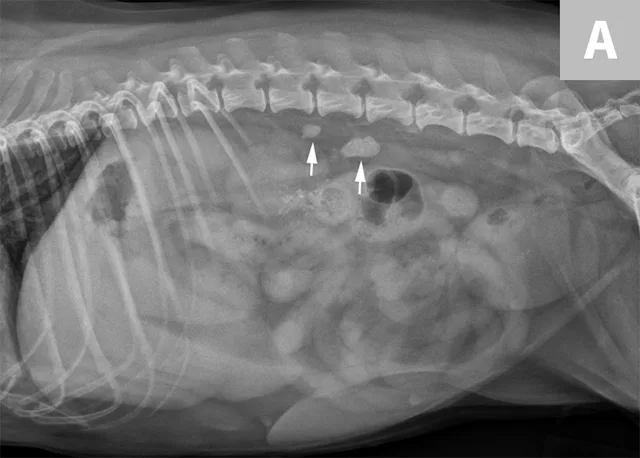

FIGURE 3A

Close-up radiograph of the left kidney with a large, smoothly margined renal calculus in a clinically normal canine patient.